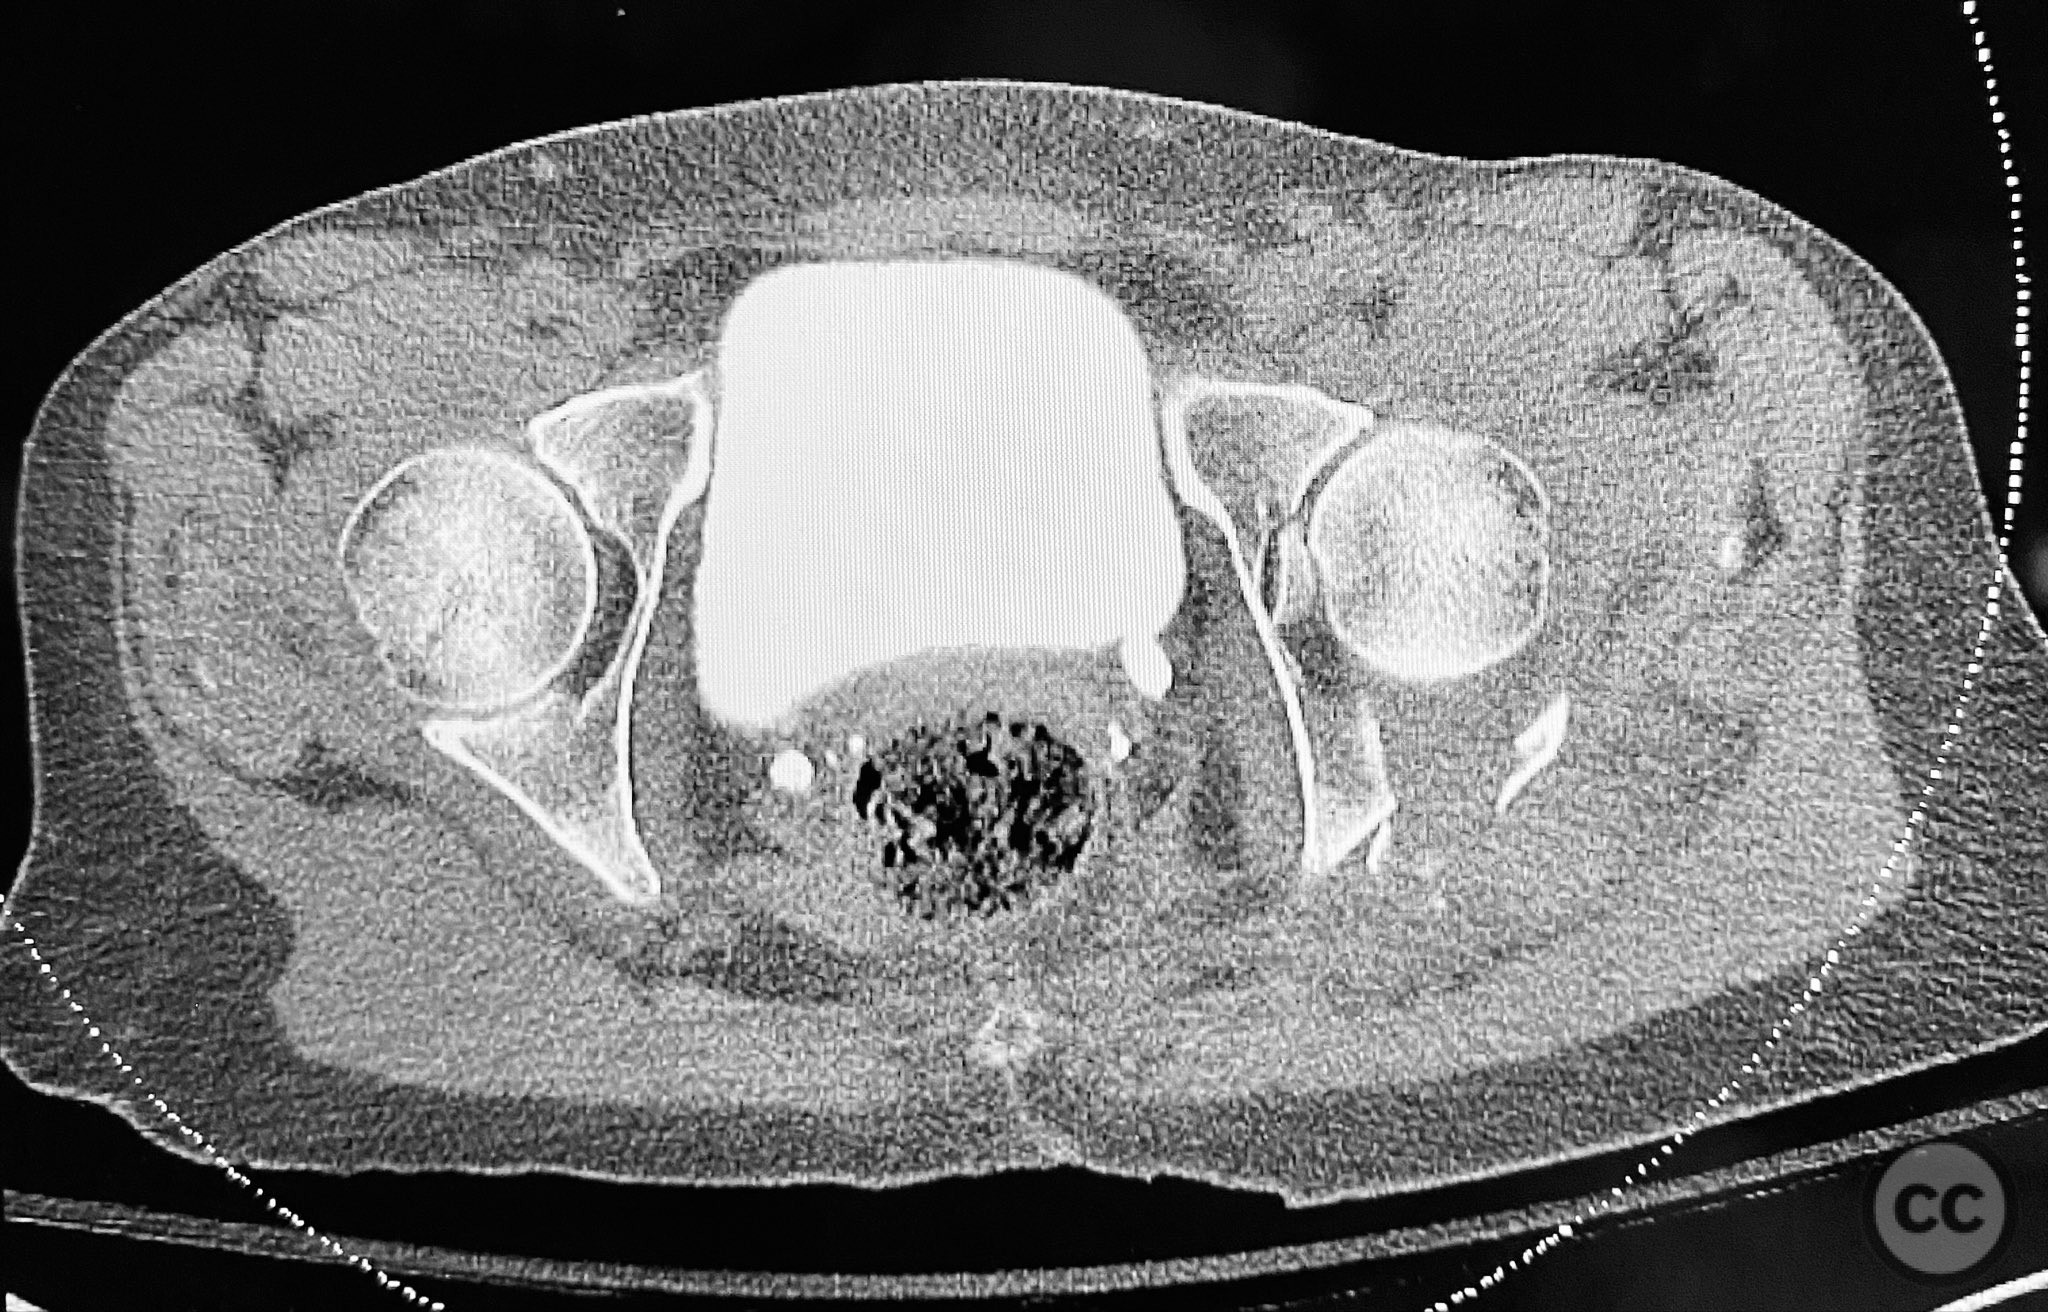

Clinical and radiological findings:  A patient sustained a posterior wall acetabular fracture-dislocation, characterized by comminution of the posterior wall, impaction of fragments into the posterior column region, and intra-articular loose fragments within the fossa acetabuli. Sagittal imaging demonstrated femoral head impalement on the intact wall, raising concern for potential irreducibility. Coronal and axial CT images revealed acetabular and femoral head impactions, peripheral wall comminution, incomplete fracture extension at the acetabular notch and quadrilateral surface, and an articular fragment within the joint. Surface renderings confirmed the extent of peripheral wall comminution and impaction. Despite these findings, a closed manipulative reduction was successfully achieved, resulting in a congruent reduction on post-reduction imaging.